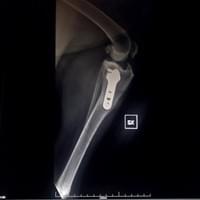

Chirurgia ortopedica

Nella nostra struttura si offre un servizio di chirurgia ortopedica tramite l’utilizzo di diverse tecniche operatorie, quali i fissatori esterni e l’utilizzo di placche e viti (fissazione interna), per il trattamento delle fratture .Per il trattamento della Rottura del legamento crociato craniale del ginocchio, si effettuano le metodiche piu’ moderne come: la TTA POROSA (tibial tuberosity advancement) e la TPLO (osteotomia livellante del piatto tibiale) .

Ci occupiamo anche delle patologie chirurgiche legate alla Displasia di rotula.